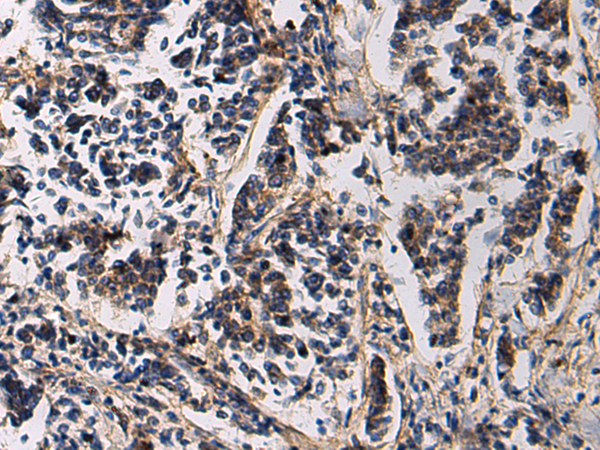

IHC positive control:

Human esophagus cancer and Human breast cancer

IHC Recommend dilution:

50-200